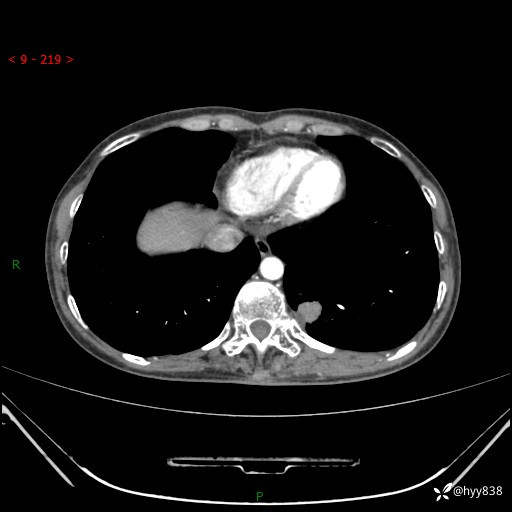

胸部CT平扫

增强动脉期+静脉期

各期CT值:48hu 65hu 76hu